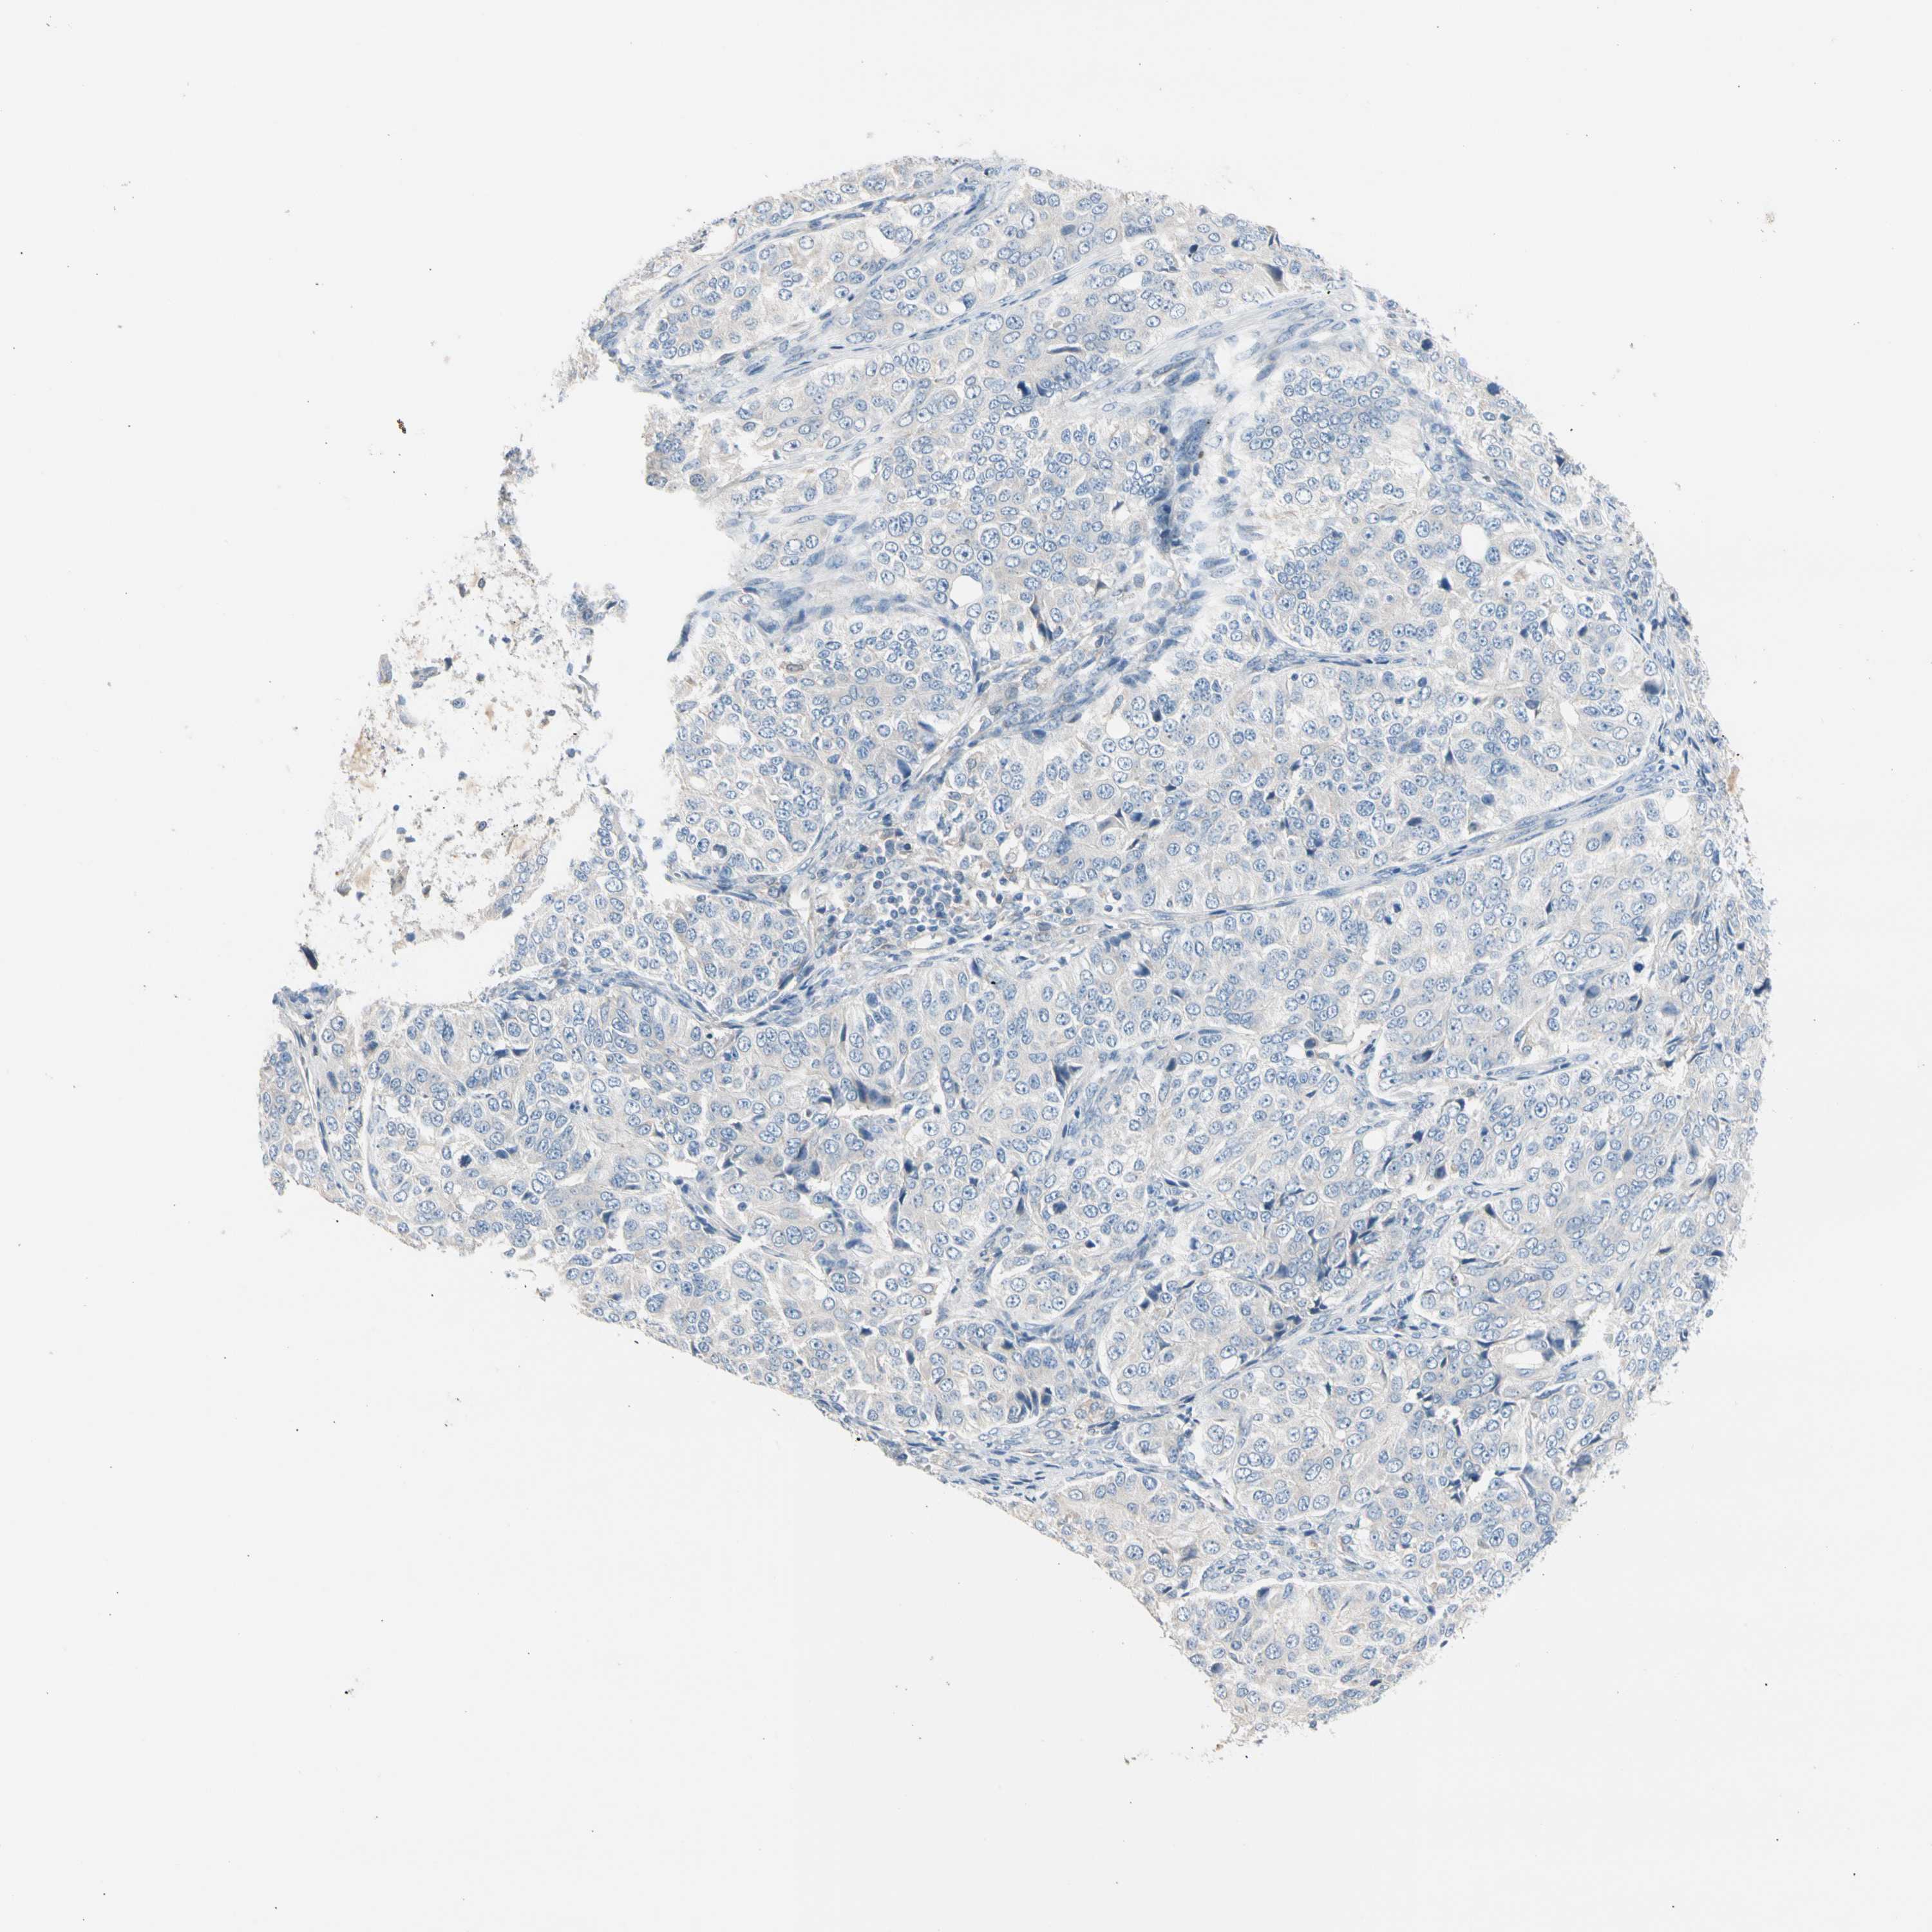

OVARIAN CANCER - Protein expressioni

A mouse-over function shows sample information and annotation data. Click on an image to view it in a full screen mode. Samples can be filtered based on level of antibody staining by selecting one or several of the following categories: high, medium, low and not detected. The assay and annotation is described here.

Note that samples used for immunohistochemistry by the Human Protein Atlas do not correspond to samples in the TCGA dataset.

Antibody stainingi

Antibody staining in the annotated cell types in the current human tissue is reported as not detected, low, medium, or high, based on conventional immunohistochemistry profiling in selected tissues. This score is based on the combination of the staining intensity and fraction of stained cells.

Each image is clickable and will lead to virtual microscopy that enables deeper exploration of all samples and also displays staining intensity scores, fraction scores and subcellular localization as well as patient and tissue information for each sample.

Cystadenocarcinoma, serous, NOS

Carcinoma, endometroid

Cystadenocarcinoma, mucinous, NOS

Carcinoma, NOS